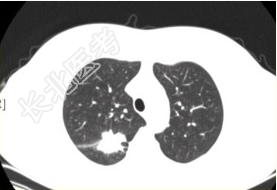

- [材料题] 患者女,54岁,无症状,常规体检透视时发现右上肺阴影。既往无结核病史。体格检查阴性。CT结果如下图。

- 多项选择题1.本病例可见的征象包括

A、分叶征

B、毛刺征

C、胸膜凹陷征

D、空泡征

E、含气支气管征

F、钙化